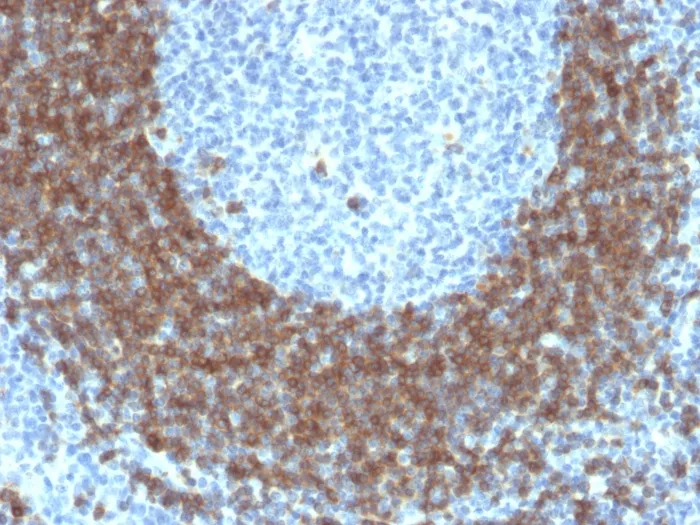

- Applications: IHC, FFPE (verified)

- Validated Applications: IHC, FFPE

- Positive Control: Daudi or Ramos cells. Germinal center B- cells in a lymph node or tonsil (IHC).